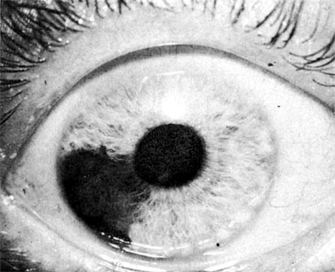

Nevi (Figures 7-7 and 7-8) are usually flat lesions with or without pigment lying in the stroma of the tissue. On the anterior surface of the iris, they may be noted as iris "freckles." Posteriorly in the choroid, one may see flat pigmented areas. Large choroidal nevi are difficult to differentiate from malignant melanomas. Their flat appearance and especially their lack of growth on repeat serial examinations are important in the differential diagnosis from malignant melanoma.

Figure 7-7

Figure 7-7: Nevus of the iris. (Courtesy of A Rosenberg.)